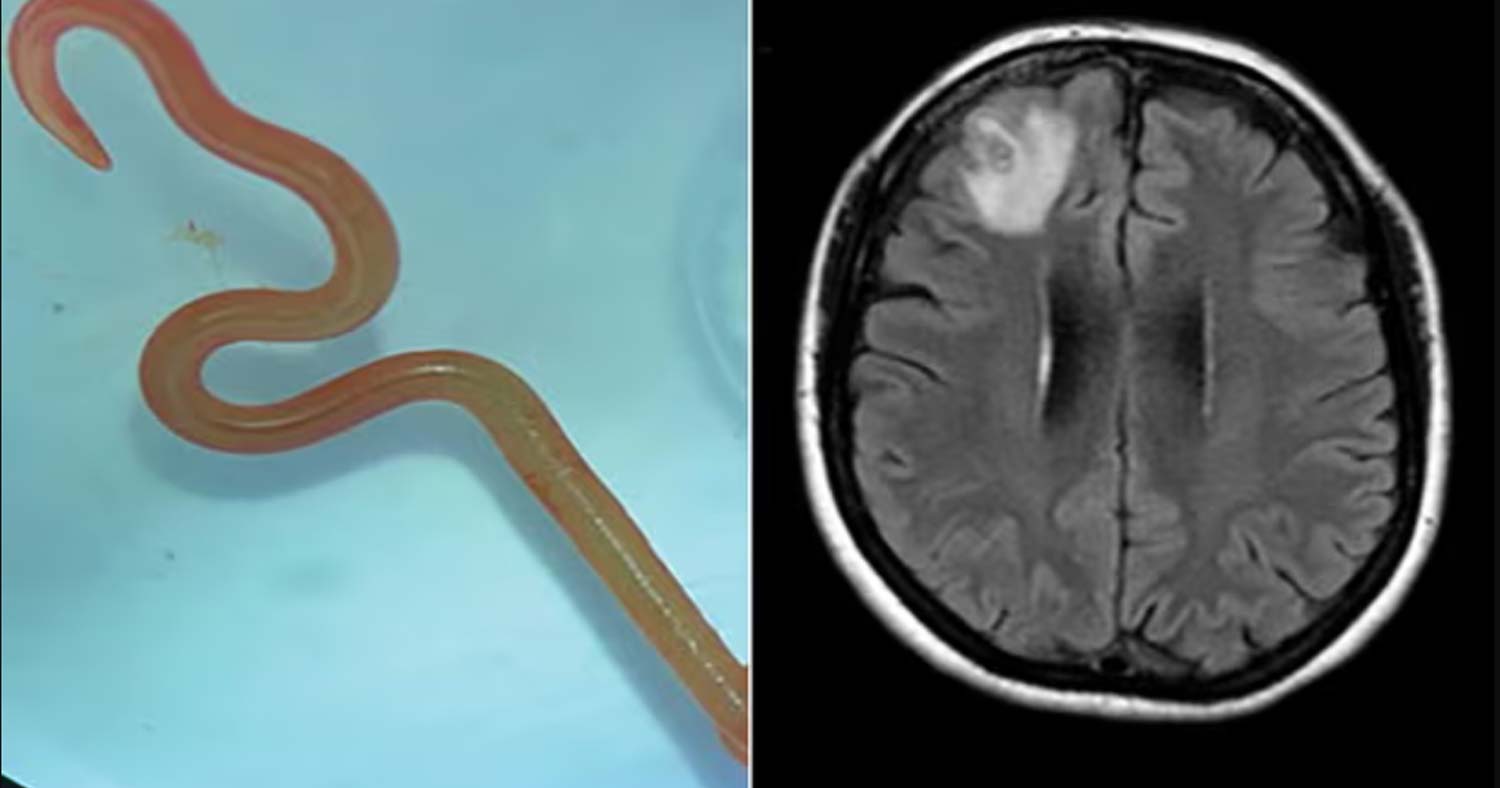

Το δείγμα του στρογγυλού σκουληκιού αφού αφαιρέθηκε από τον εγκέφαλο της γυναίκας. Φωτογράφος: Canberra Health

Σε μια ακτινογραφία που έκανε, ανακαλύφθηκε από τους γιατρούς «μια άτυπη βλάβη εντός του δεξιού μετωπιαίου λοβού του εγκεφάλου» αλλά ο πραγματικός λόγος της κατάστασής της αποκαλύφθηκε από έναν χειρουργό κατά τη διάρκεια μιας βιοψίας τον Ιούνιο του 2022.